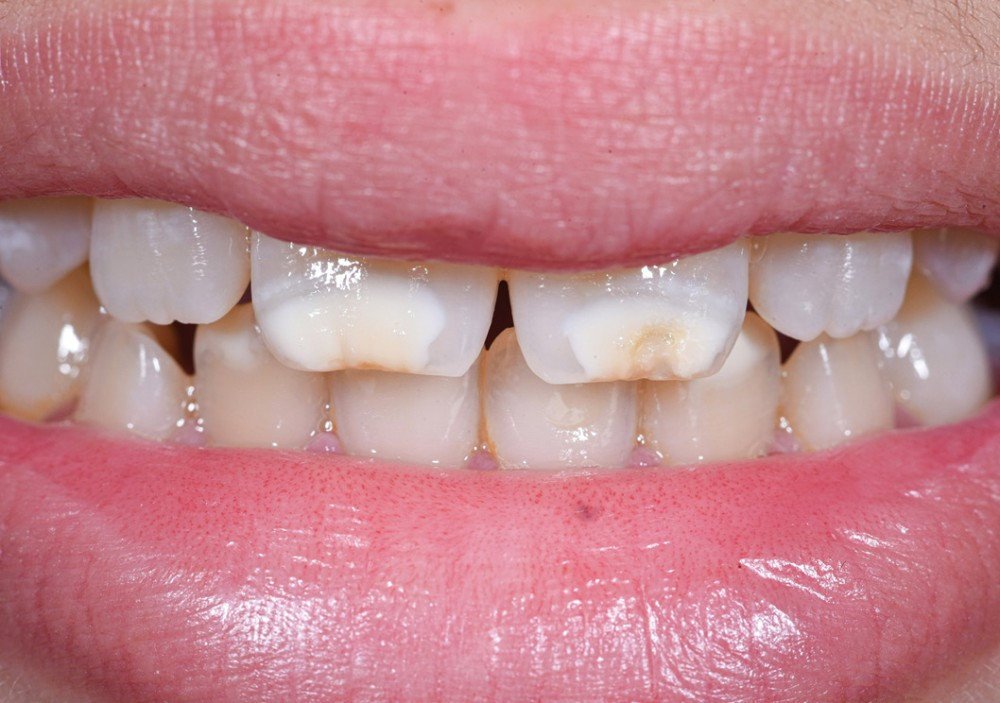

Hypocalcification de l’émail — Se manifeste par des taches blanchâtres crayeuses sur la surface dentaire. Elle peut être d’origine locale ou systémique.

Hypoplasie due aux tétracyclines — Les antibiotiques de la famille des tétracyclines, pris pendant la grossesse ou chez l’enfant avant l’age de 8 ans, peuvent provoquer des taches jaunes, brunes ou grises affectant un groupe ou l’ensemble des dents.

Amélogenèse imparfaite héréditaire — Dysplasie ou hypocalcification héréditaire se caractérisant par des plaques opaques représentant un émail déminéralisé et cassant. La dent est brune au début, puis fonce après éruption. Cette pathologie nécessite souvent une réhabilitation complète.

Fluorose dentaire — Peut être discrète, modérée ou sévère selon le niveau d’exposition au fluor. Elle se distingue d’autres anomalies par des lésions symétriques sur les dents.